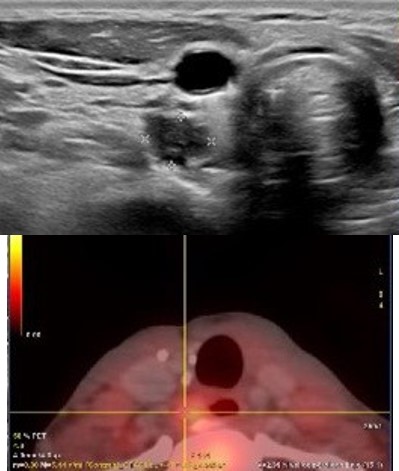

Surgical excision was considered. Fine-needle aspiration (FNA) of the paraesophageal node revealed mature lymphoid cells with low cellularity. Based on clinical and imaging findings, left lymph node dissection was performed. Histopathology confirmed parathyroid carcinoma in infraclavicular and retrocarotid lymph nodes (Figure 2).

Figure 2: (A) Parathyroid carcinoma implant. (B) Positive immunohistochemical study.

PC remains a diagnostic challenge. Clinical suspicion should be raised by suggestive findings such as calcium >14 mg/dL, cervical lesions >3 cm, renal (nephrolithiasis, nephrocalcinosis) and skeletal abnormalities (osteoporosis, vertebral fractures). Definitive diagnosis relies on histopathological evaluation (Figure 2).